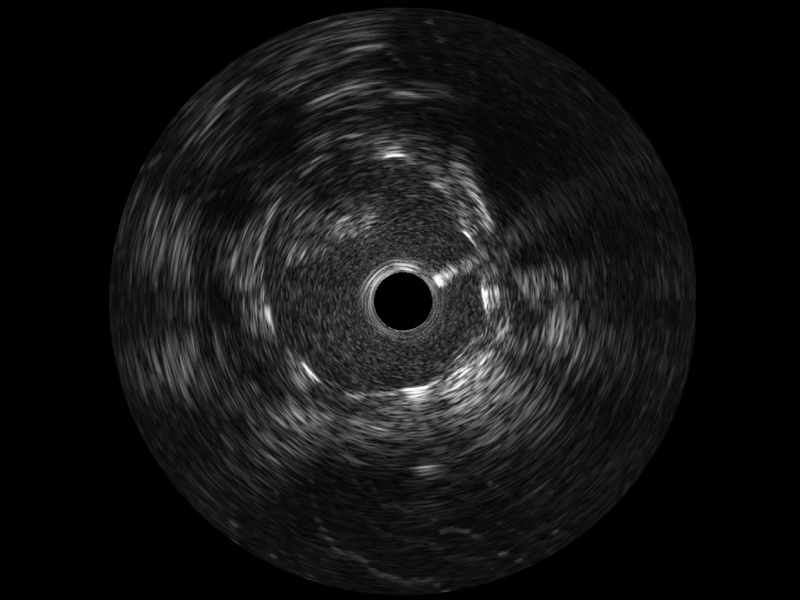

• 传统IVUS图像

对比传统IVUS导管成像,米兰官方网站宽频IVUS图像的近场支架梁显影更细腻,远场中膜外血管仍清晰可辨,兼顾远中近,兼顾分辨力与穿透深度